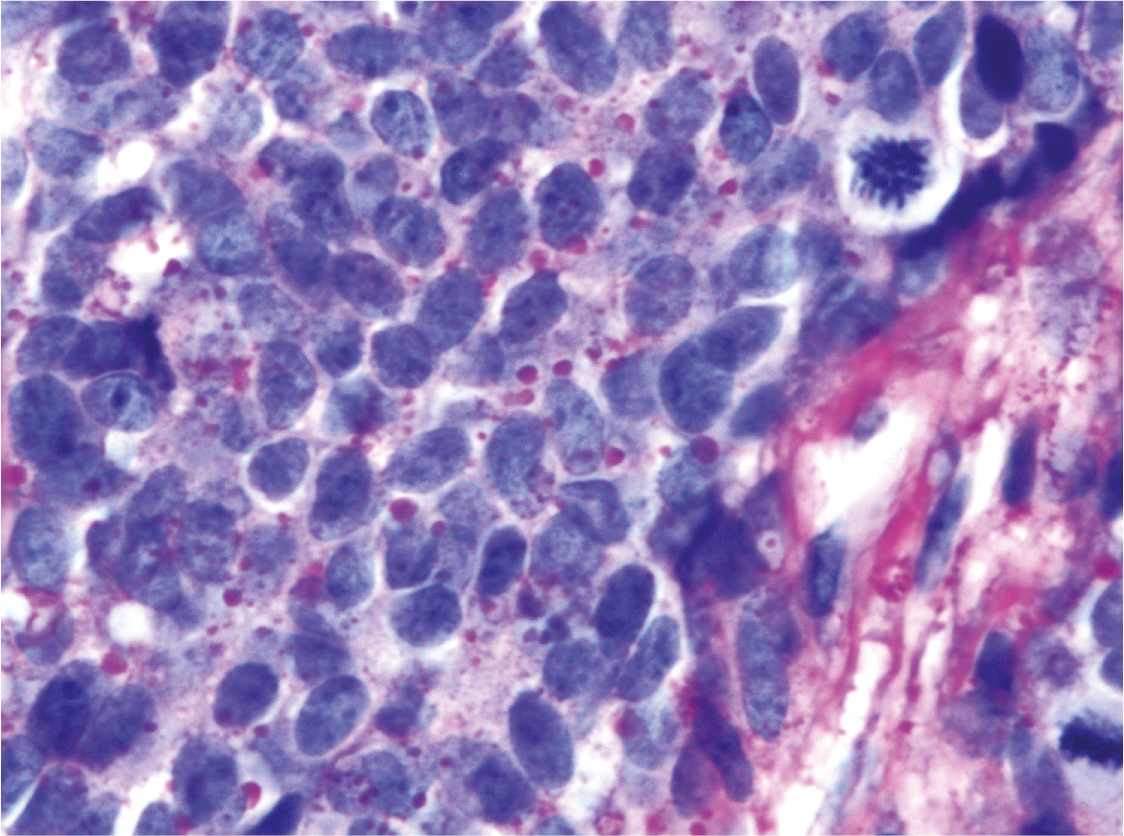

Fig 3

Figure 3. CD99 expression in ES/PNET. Immunohostochemistry of Ewing sarcoma/Primitive neuroectodermal tumor (ES/PNET) showing an intense membranous staining. It is imperative to emphasize that FLI1 immunohistochemistry is standard of care because of the non-specificity of the CD99 antigen. Thus, a positive CD99 staining result must be validated by a nuclear FLI1 immunohistochemical result, which is not demonstrated here. FLI1 is the surrogate marker for characteristic EWSR1-FLI1 translocation. A minority of ES/PNET disclose a translocation involving the EWSR1 gene and an alternative partner, most commonly the ERG gene, which is located on 21q12. (Avidin-Biotin Complex, anti-CD99 immunostaining, x400 original magnification).